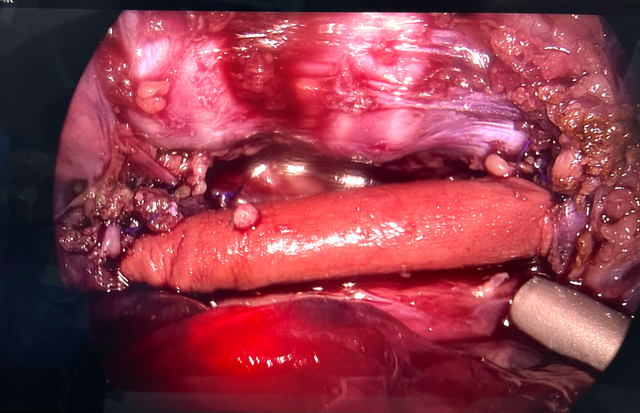

胸腔镜下分离显露食管

胸腔镜下手术切除食管及CEI食管吻合成功